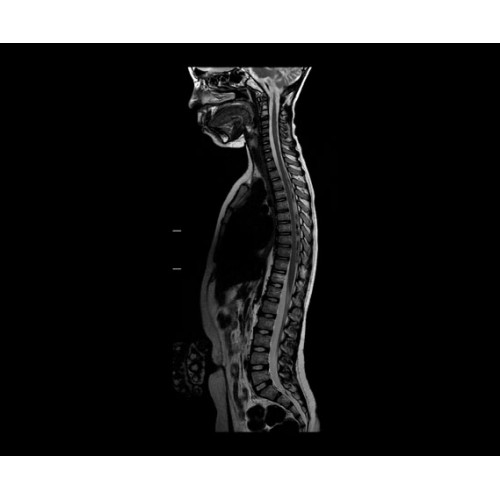

SIGNA PET/MR 3.0T — это гибридная система, в которой совмещаются две принципиально разные технологии — магнитно-резонансную томографию (МРТ) и позитронно-эмиссионную томографию (ПЭТ). Система отличающийся высокой чувствительностью и эффективностью и предназначена для диагностики в области онкологии, неврологии, кардио-васкулярных исследований, исследований воспалительных процессов.

Компания GE Healthcare представляет революционную, полностью интегрированную систему SIGNA PET/MR1, в которой сочетаются времяпролетная технология (TOF) и возможности напряженности магнитного поля 3.0 Тл. Мы поможем вам поднять исследования на более высокий уровень. SIGNA PET/MR позволяет достичь впечатляющей точности и скорости исследований, а благодаря новейшей технологии реконструкции Q.Clear2 качество изображений улучшается в два раза. Кроме того, в систему включен полный набор клинических приложений и гибких катушек для проведения любых видов исследования, открывая для вас возможности визуализации, о которых вы даже не догадывались.

В систему SIGNA PET/MR встроены запатентованные детекторы кремниевого фотоумножителя (SiPM) и сверхчувствительные кристаллические сцинтилляторы на основе лютеция толщиной 25 мм. Благодаря этому обеспечивается исключительная чувствительность и возможность использования времяпролетной диагностики (TOF).

Кроме того, в результате использования технологии TOF и инновационной технологии реконструкции Q.Clear вы сможете добиться прекрасного соотношения сигнал/шум. А благодаря технологии нулевого времени эхо (ZTE) визуализировать костную структуру без ионизирующего излучения. Все эти разработки для улучшения качества сканирования и точности анализа помогут вам использовать весь потенциал ПЭТ/МРТ.